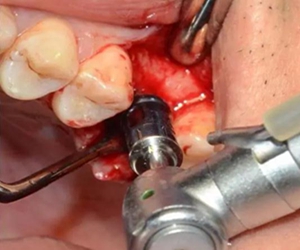

用配套工具進行水壓式?jīng)_頂,提升竇膜。手感力反饋和回吸正常。在沖壓水量上要控制,緩慢反復(fù)多次抽吸,確保竇粘膜提升均勻。